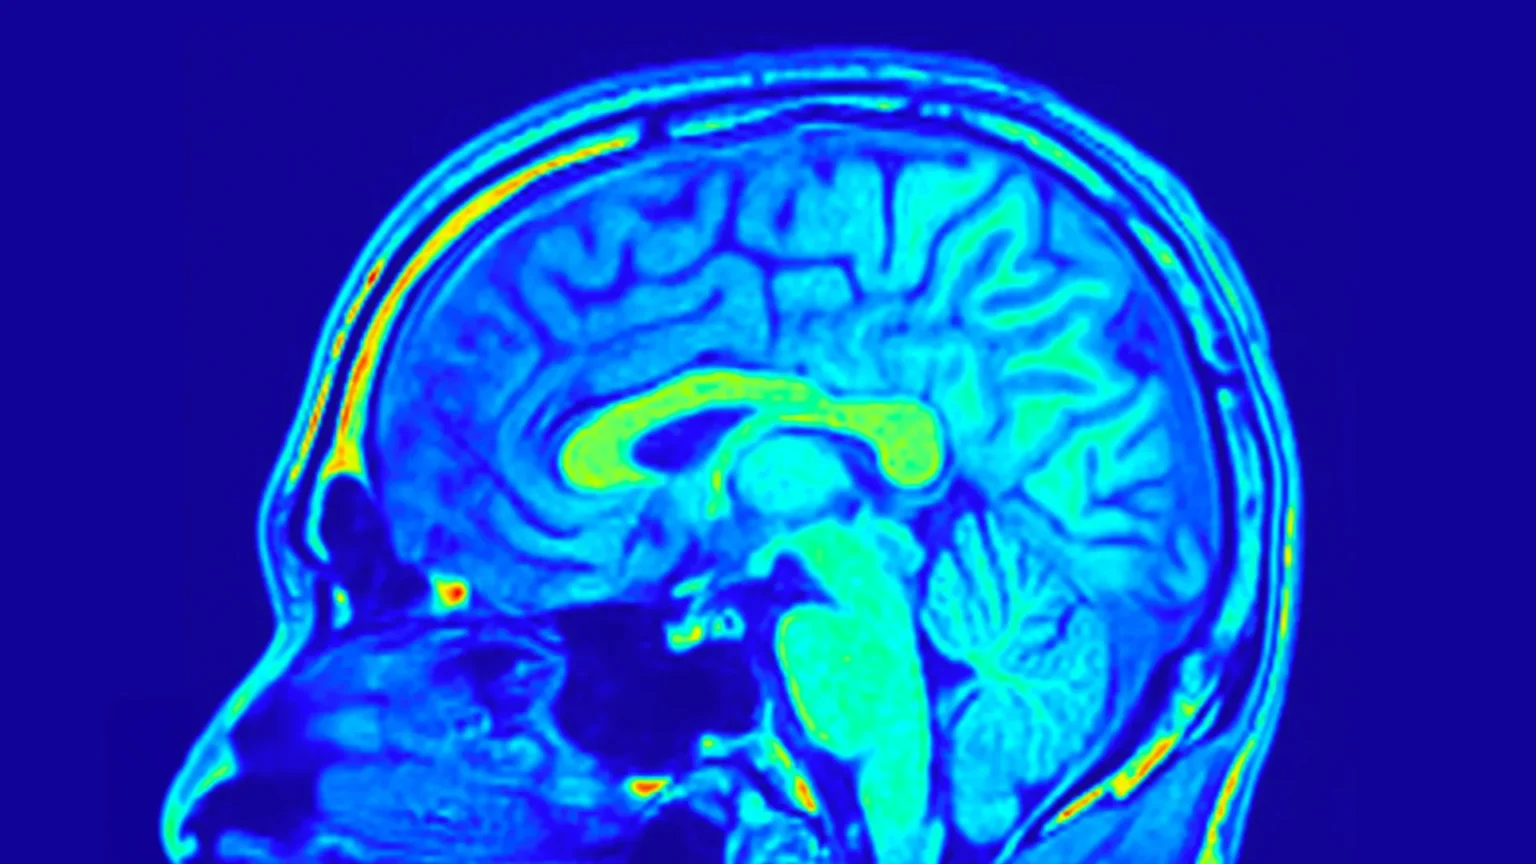

Ερευνητές ανακάλυψαν ότι τμήματα του ανθρώπινου εγκεφάλου γερνούν πιο αργά από ό,τι πιστευόταν μέχρι σήμερα, ιδιαίτερα στην περιοχή που επεξεργάζεται την αίσθηση της αφής. Χρησιμοποιώντας μαγνητικές τομογραφίες εγκεφάλου εξαιρετικά υψηλής ανάλυσης, διαπίστωσαν ότι ενώ ορισμένα στρώματα του εγκεφαλικού φλοιού λεπταίνουν με την ηλικία, άλλα παραμένουν σταθερά ή ακόμα και παχαίνουν, υποδηλώνοντας μια αξιοσημείωτη ικανότητα προσαρμογής.

Χρησιμοποιώντας μαγνητική τομογραφία (MRI), οι ερευνητές μπόρεσαν να χαρτογραφήσουν αυτή την περιοχή του εγκεφαλικού φλοιού με πρωτοφανή ακρίβεια. Για να το πετύχουν, χρησιμοποίησαν έναν ιδιαίτερα ευαίσθητο σαρωτή με μαγνητικό πεδίο επτά Tesla, επιτρέποντάς τους να απεικονίσουν μικροσκοπικές δομές του εγκεφάλου με μέγεθος περίπου όσο ένας κόκκος άμμου. Συνολικά εξετάστηκαν περίπου 60 γυναίκες και άνδρες μεταξύ 21 και 80 ετών.